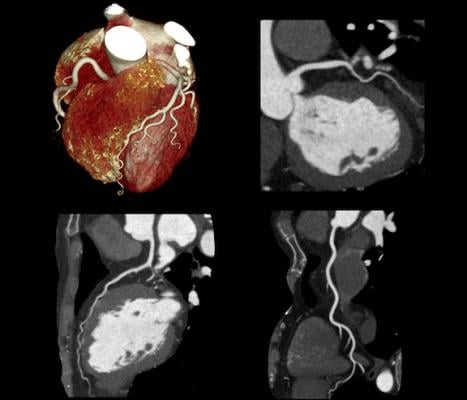

Coronary CT angiography images courtesy of Canon Medical Systems.

According to Leslee Shaw, Ph.D., MSCCT, chair and lead author of the expert consensus: “Coronary computed tomographic angiography (CCTA) provides a wealth of clinically meaningful information. This consensus will serve as a guide given that previously, there has been no uniform agreement on how to identify and quantify the presence or absence of nonobstructive atherosclerosis and high-risk plaque features as precursors for incident coronary events or their use in evidence-based clinical decision-making.”

Growing evidence over the past decade has accumulated regarding the prognostic significance of nonobstructive and obstructive atherosclerotic plaque and its importance for estimating patient risk and guiding preventive care. Rigorous documentation of atherosclerosis on CCTA provides a vital opportunity to make recommendations for preventive care and to initiate and guide an effective care strategy for at-risk patients.